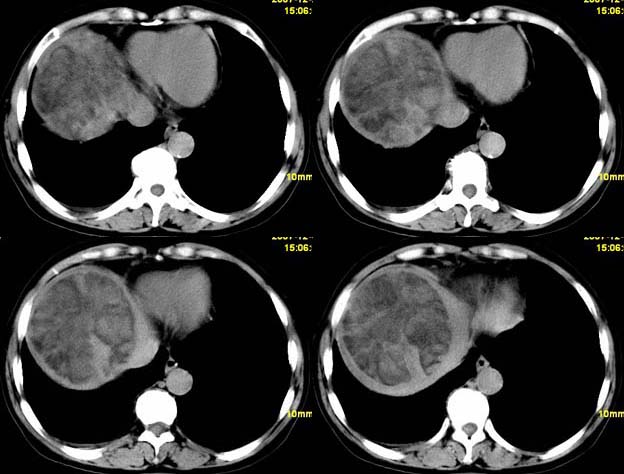

标题: CT11039:肝脏占位,平扫加增强,很“漂亮”的图像。

女,67,自诉右上腹痛10天,余病史未提供。

平扫低密度ct值约-14hu.